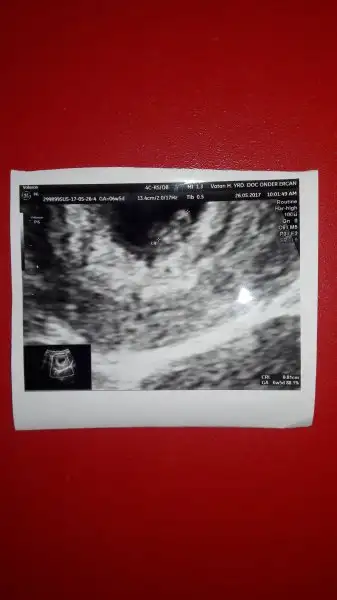

birazdan doktora geçeceğim.heyecan tqvan yapmis durumda. sanki ilk gebeligim.

Güzel haberlerle gel inşallah bende 3.40 da gideceğimbirazdan doktora geçeceğim.heyecan tqvan yapmis durumda. sanki ilk gebeligim.

Güzel haberlerle gel inşallah bende 3.40 da gideceğim

evet bende merak ediyorum canım inşallah sağlıkla kavuşuruz bebişlerimize...inşallah kesen görülecek kadar büyümüştür çok merak ediyorum ya sıra bana da gelse